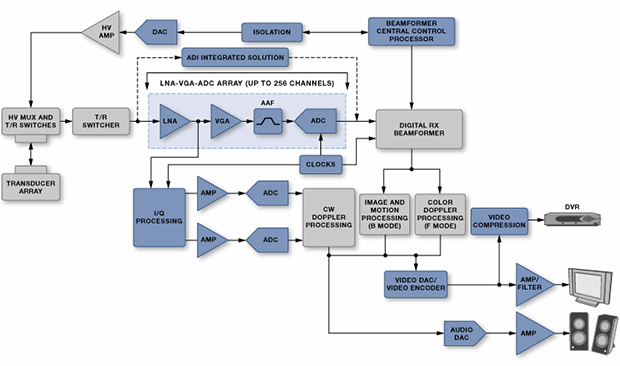

Ultrasound is effectively a high-frequency sonar system, measuring the minute echoes of sound waves as they pass through the body. Ultrasound images (see Figure 8) resemble x-rays except that they are displayed in real-time.

The task of accurately measuring and discriminating ultrasound echoes is difficult because it is increasingly the second harmonic that is being detected rather than the fundamental. This can be done by suppressing the second harmonic in the transmit signal so that only return signals have that frequency; this requires an almost perfect 50% duty cycle on the pulse train. Alternatively, positive and inverted versions of the signal can be generated so that they can cancel out to reveal underlying harmonics. In order for this to work the rise and fall times of the pulsers must match as closely as possible so that their spectra cancel. These requirements place severe restrictions on the high-voltage pulsers. Figure 9 shows a typical ultrasound system.

Figure 9: An ultrasound system (Courtesy of Analog Devices).

Doppler processing used to detect movement makes the design more complex yet. The whole concept relies on the transceiver side to send a high-power signal and then the receiver side to pick up a faint response. In fact, the receiving side needs to be blanked using a transmit/receive (T/R) switch when transmitting so that it is not overwhelmed – but it then has to be turned back on in time to catch the return.

The cost, power, and size requirements, especially for portable units, have driven increased integration. For example, TI’s LM96570 is an eight-channel integrated beamformer, while the LM96511 integrates the LNA, VGA, and a 12-bit continuous time ΔΣ ADC into a single receive analog front end (AFE). The LM96530 is an integrated T/R switch. Maxim, meanwhile, provides the MAX2079, an eight-channel integrated receiver front end with continuous-wave (CW) doppler beamformer. The MAX4940 is a high-voltage pulsar, and the MAX4936 is their T/R switch.